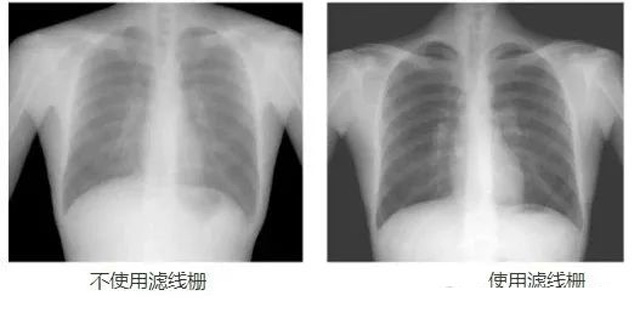

DR影像X射線在醫(yī)學檢查成像有著廣泛的使用。但是它的散射線影響成像質(zhì)量問題。濾線柵的發(fā)明使用很好的解決了這個問題,構(gòu)造簡單鉛條粗,密度和柵比規(guī)格單一,能減散射線但吸收較多原發(fā)射線。伴隨這醫(yī)療影像設(shè)備技術(shù)的發(fā)展,這個濾線柵的工藝制造技術(shù)有改進,鉛條變薄,柵密度和柵比有更多的選擇。特別是材料方面有新組合,填充物也依不同成像要求優(yōu)化。特別是移動DR這類型的DR設(shè)備的出現(xiàn),濾線柵也設(shè)計成立方便拆卸形的,方便使用。被照體情況決定是否使用,更好平衡成像質(zhì)量與射線劑量。